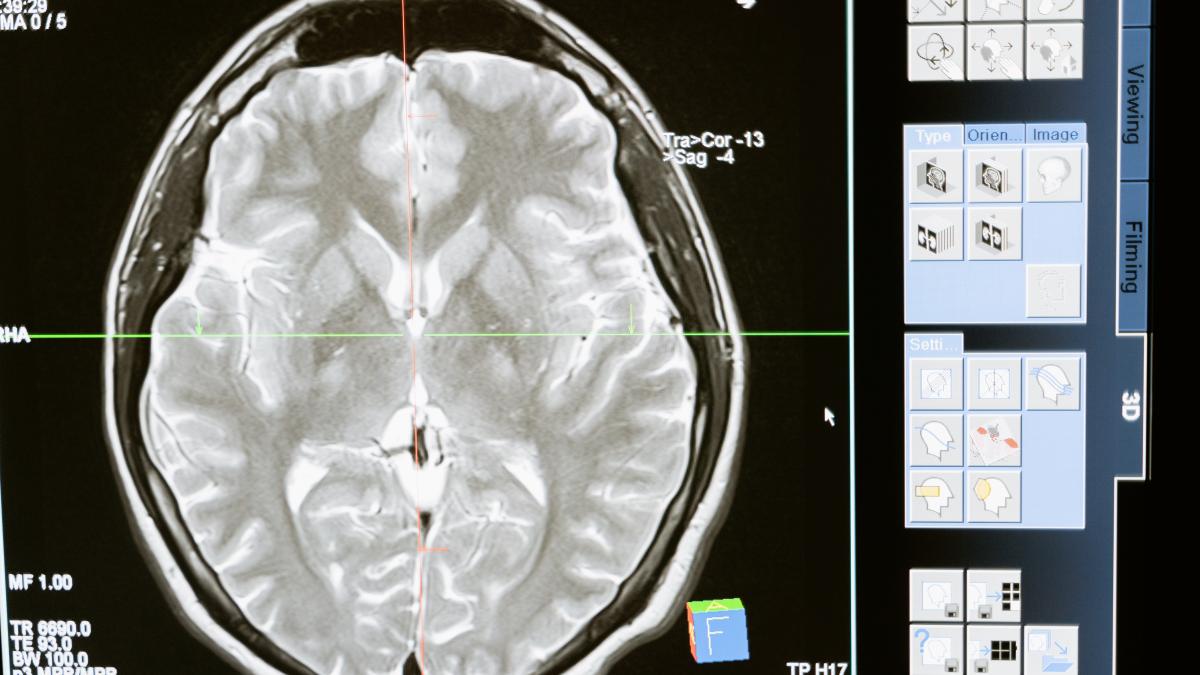

Speranțe pentru tratarea cancerului cerebral: Cercetătorii au descoperit un medicament 100% eficient în tratamentul glioblastomului

Cercetătorii americani au demonstrat că un medicament-gel, derivat din combinația dintre un medicament anticancer și un anticorp, este capabil să vindece 100% tumorile cerebrale la șoareci. Această descoperire oferă speranțe pentru un nou tratament pentru glioblastomul uman.

Cercetătorii americani au dezvoltat un gel inovator capabil să trateze cu o eficacitate de 100% șoarecii care suferă de glioblastom, cea mai comună, agresivă și mortală tumoare cerebrală la om.